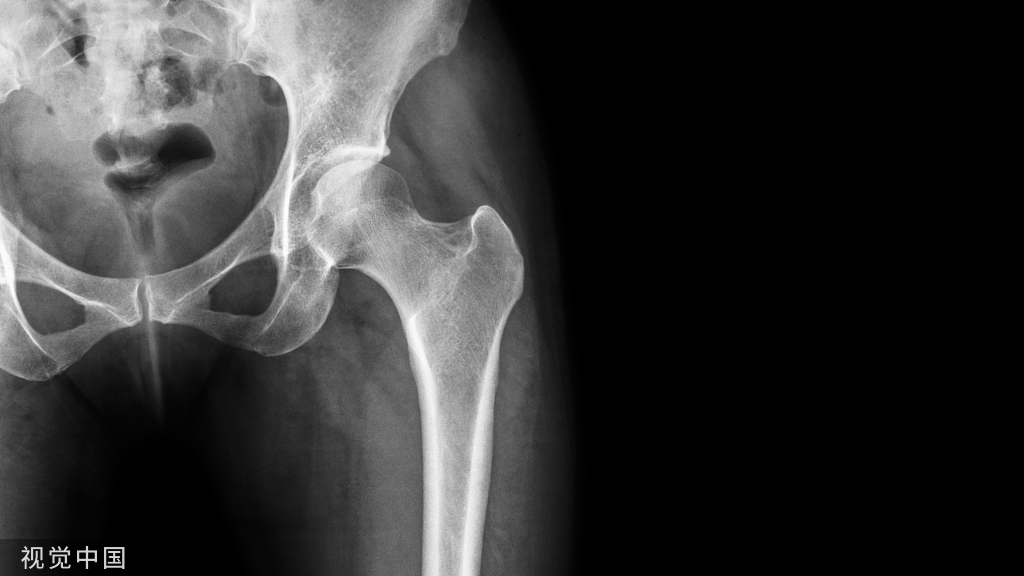

被冤枉的足跟骨刺

如下图(红色箭头所指),跟骨骨刺看着就让人觉着疼,所以“骨刺”在大家心目中被妖魔化成了足跟痛的罪魁祸首。但其实足跟骨刺并不是导致脚底跟疼痛的原因,研究表明,有足跟骨刺的人群中,63%的人是没有任何的疼痛症状。

足跟骨刺是跟骨骨质的增生,跖筋膜活动过多,过度收缩变得紧张,造成跖筋膜有细微的撕裂和发炎变得不舒服,造成了跖底筋膜炎这时人体的自我保护机制形成骨刺,想要保护过度收缩的而受伤的跖筋膜。